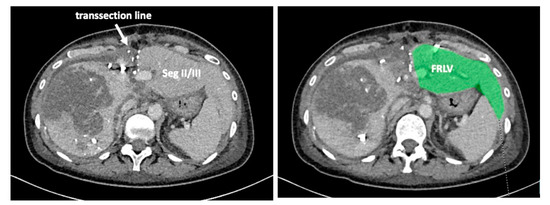

To complete in-situ splitting, the liver capsule is incised on the right side of the falciforme ligament and in the sulcus arantii. The parenchyma between segments II/III and I/IV is then divided (Figure 3). The structures to be transected in the future, i.e., all arterial and biliary branches to segments I and IV-VIII, as well as the right and middle hepatic veins, are marked by vessel loops that are fastened with titanium clips avoiding strictures of the vessels (Figure 4 and Figure 5). These remain in situ for easier identification during the second procedure. The future resection specimen is enveloped in a plastic foil (3M™ Steri ™ Drape Isolationsbeutel, 1003, 49 cm × 49 cm) to prevent adhesions in particular to the vena cava and at the resection margin.

On day 7 after the operation, CT-volumetry and, potentially, (99 m)Tc-mebrofenin-hepatobiliary-scintigraphy are performed. Alternative function tests may be used, according to the centers’ experience. We strongly recommend repeating the volumetric and functional analyses with the identical technique as used before the first step of the operation. This is repeated on a weekly basis until the necessary volume and function are reached (Figure 6). After sufficient growth of the remnant liver volume, i.e., a volume of >0.6% of the body weight or >25% of functional liver volume, and a cut-off value in the scintigraphy of 2.7%/min/m2 is achieved, completion hepatectomy is scheduled. In the case of prior chemo- or immunotherapy, the cut-off value of functional liver value may vary and additional investigations such as a (99 m)Tc-mebrofenin-hepatobiliary-scintigraphy are even more important. Some authors advocate more than 35% of functional liver volume in these conditions. During the second operation, a thorough exploration of the abdomen is performed, and the plastic foil is removed (Figure 7). Under the guidance of the vessel loops the previously marked arterial and biliary branches to the resection specimen, as well as the right and middle hepatic veins are divided, and the specimen is removed. If necessary, reconstructions of vessels and biliary structures are performed (Figure 8 and Figure 9).

Figure 3. A complete transsection between liver segments II/III and I/IV is recommended to render the second procedure as easy as possible. (A): During the first procedure. The vena cava is easily seen. (B): During the second procedure after division of the arteries and bile ducts to the right and caudate lobe. Removal of the resection specimen is safe and fast without further preparation or dissection.

Figure 6. The functional residual liver volume (FRLV) is measured on a weekly basis until a sufficient volume is reached.